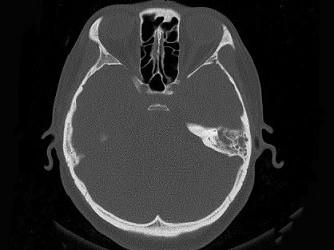

女,34岁,左耳鸣,听力下降两个月,PE:左外耳道有脓性分泌物,鼓膜充血水肿,左中耳腔内软组织影,CT检查如图,最可能诊断为 ( )